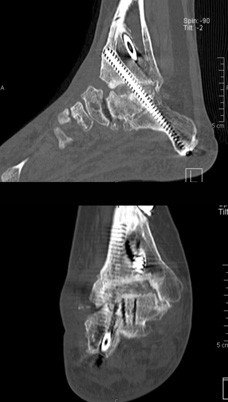

Zur weiteren Diagnostik erfolgte die Durchführung einer Computertomographie. Hier zeigt sich eine partielle Nekrose im Bereich der durchgeführten Arthrodese des oberen Sprunggelenkes. Vermutlich hat ein Teil des seinerzeit eingebrachten Knochens keinen adäquaten Anschluss an die Durchblutung gefunden und ist nekrotisiert.

Inzwischen sind vier Monate seit der letzten Operation vergangen. Die Heilung im Bereich des rearthrodesierten oberen Sprunggelenkes verläuft regelrecht. Sechs Wochen nach der Operation wurde eine CT-Untersuchung zur Beurteilung der Situation durchgeführt. Die Aufnahmen zeigten eine beginnende knöcherne Durchbauung und ein Einwachsen des eingebrachten Fremdknochens.